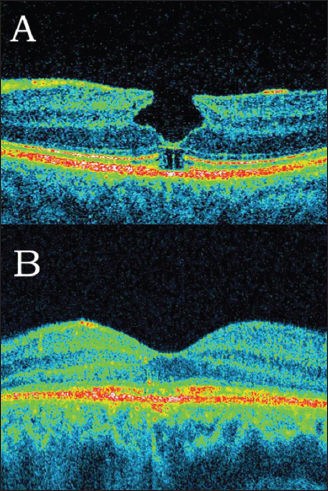

Since the introduction of pars plana vitrectomy as the method of choice in full-thickness macular hole treatment, the success rate has reached almost 100%.17-24 However, in some patients, especially with large, longstanding macular holes, incomplete improvement of visual acuity is observed immediately after surgery. This outcome is due to different defects of the particular retinal layers, which can be observed on SD-OCT (Figure 3). IS/OS defects have been reported to have the strongest influence on visual acuity.

Figure 3A (top). SD-OCT one month after macular hole surgery. A hyporeflective area beneath the outer nuclear layers is visible. The junction between the inner and outer segments of photoreceptors (IS/OS) is incomplete. (B, bottom) SD-OCT 12 months after macular hole surgery. Complete restoration of the IS/OS line is observed.

Recently, several authors have analyzed postoperative changes in retinal morphology after macular hole surgery, and it was proved that visual acuity may improve for at least 12 months after surgery.23

Improvement of visual acuity corresponds with improvement of morphology in the outer retinal layers and with restoration of the IS/OS line. Michalewska et al. reported on 71 eyes, among which 93% had photoreceptor defects one week after surgery, and 29.5% had defects 12 months after surgery. The linear photoreceptor defect continuously decreased in size with time (from a mean of 882 µm one week after surgery to 60 µm 12 months after surgery).